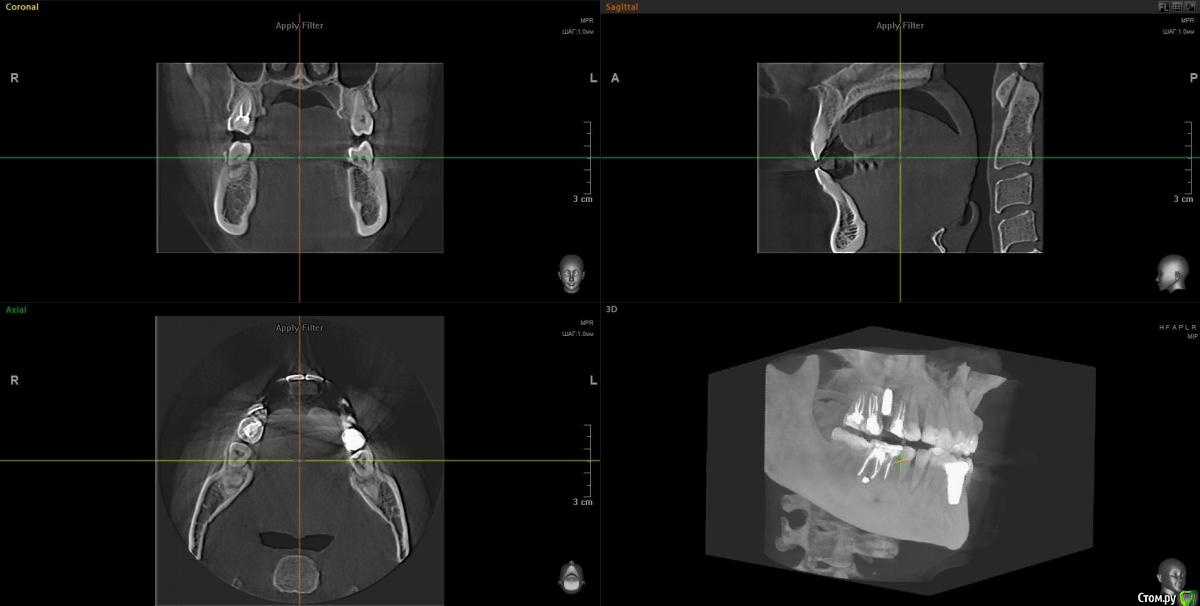

Tatiana72 Опубликовано 27 октября, 2020 Автор Поделиться Опубликовано 27 октября, 2020 Добрый вечер!Выкладываю скрины срезов Ссылка на исследованиеhttps://yadi.sk/d/ViQR0U6R2QjHzg Ссылка на комментарий

Дмитрий М Опубликовано 28 октября, 2020 Поделиться Опубликовано 28 октября, 2020 Добрый вечер!Выкладываю скрины срезовImage4.jpgImage5.jpgImage9.jpg Ссылка на исследованиеhttps://yadi.sk/d/ViQR0U6R2QjHzg не волнуйтесь всё хорошо, по КТ корень зуба не задетесть небольшой очаг разряжения на одном из апексов, обратитесь к стоматологу 1 Ссылка на комментарий